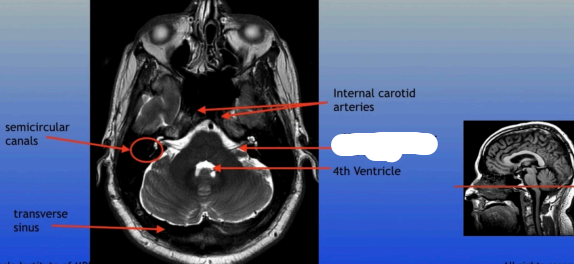

Semicircular Canals

Transverse Sinus

Internal Carotid Arteries

4th Ventricle